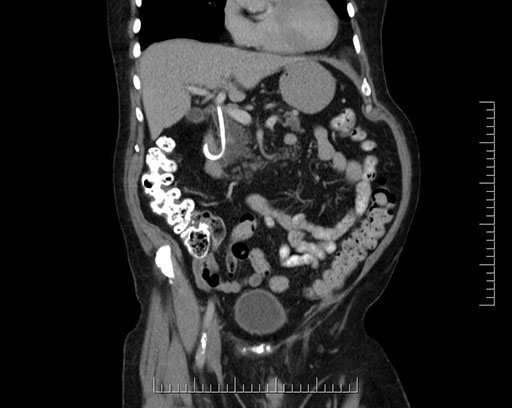

Imaging Analysis

Look through the patient's CT scan to identify any areas of concern for the necessary procedure.

Based on your CT findings, which issue(s) would give reason for "planned slowing down moment(s)" in this case?

Considering a standard Whipple procedure, what step(s) of the operation would you do differently in this case?